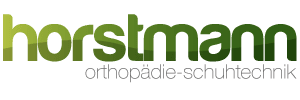

Fersenkeil aus Silikon oder Gel (schnelle Hilfe)

Ein weiches Fersenpolster, oft in Form eines Fersenkeils, kann eine schnelle Hilfe bei der Behandlung von Fersensporn sein. Dieses Hilfsmittel dient zur Dämpfung des Aufpralls sowie zur Verringerung des Drucks und der Belastung auf den Fersensporn beim Gehen oder Stehen.

- Dämpfung: Das Gel in diesen Polstern ist in der Lage, Stoßkräfte zu absorbieren, die entstehen, wenn die Ferse auf den Boden trifft. Dies kann die Menge an Stoßenergie, die auf den Fersensporn einwirkt, reduzieren und so helfen, Schmerzen zu lindern.

- Druckverteilung: Die Polster können auch dazu beitragen, den Druck auf die Ferse gleichmäßiger zu verteilen. Anstatt das gesamte Gewicht auf den schmerzhaften Fersensporn zu konzentrieren, verteilt das Polster die Last über eine größere Fläche. Dies kann helfen, die Belastung auf den Fersensporn zu reduzieren und weiteren Schaden zu verhindern.

- Fersenerhöhung: Durch die Erhöhung der Ferse kann die Spannung in der Plantarfaszie und auch der Achillessehene reduziert werden, indem sich der Winkel zwischen Fuß und Unterschenkel verändert und somit der Zug auf die Plantarfascie während des Gehens und Stehens veringert wird. Die Ferse geht nach oben, der Vorfuß geht nach unten. Die Höhe sollte unter einem Centimeter liegen und beiderseits erfolgen um keinen Beckenschiefstand zu provozieren. Biomechanische Fehlbelastungen sollten vermieden werden.

Ein Fersenpolster sollte in einem gut sitzenden Schuh getragen werden und richtig positioniert sein, so dass es direkt unter der schmerzhaften Stelle liegt. Es kann sowohl in Alltagsschuhen als auch in Sportschuhen getragen werden und eignet sich für die meisten Aktivitäten. Sie werden immer paarweise geliefert und sollten unter beiden Fersen getragen werden, damit kein Beckenschiefstand entsteht. Bei anhaltenden Schmerzen trotz der Verwendung eines Fersenpolsters, sollte ein Arzt oder Physiotherapeut hinzugezogen werden.